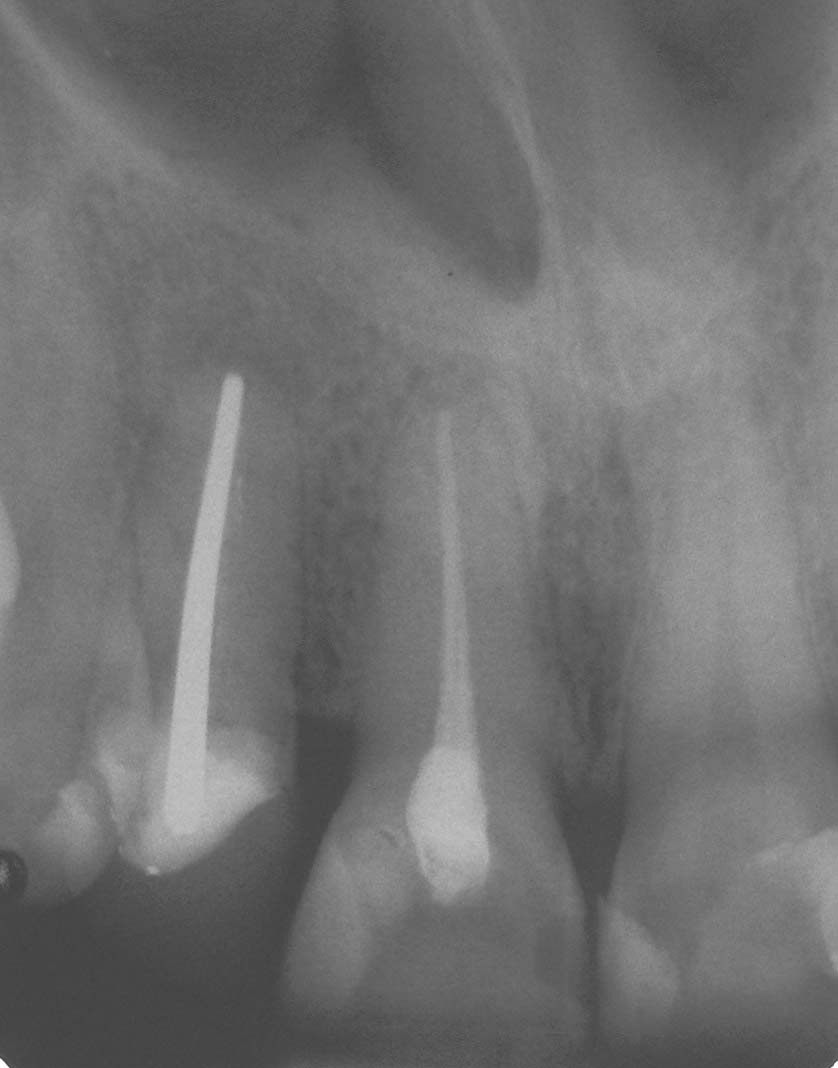

Zustand nach WSR a.l.

Veröffentlicht 8. Januar 2009 am 838 × 1068 in Wurzelspitzenresektion (1)